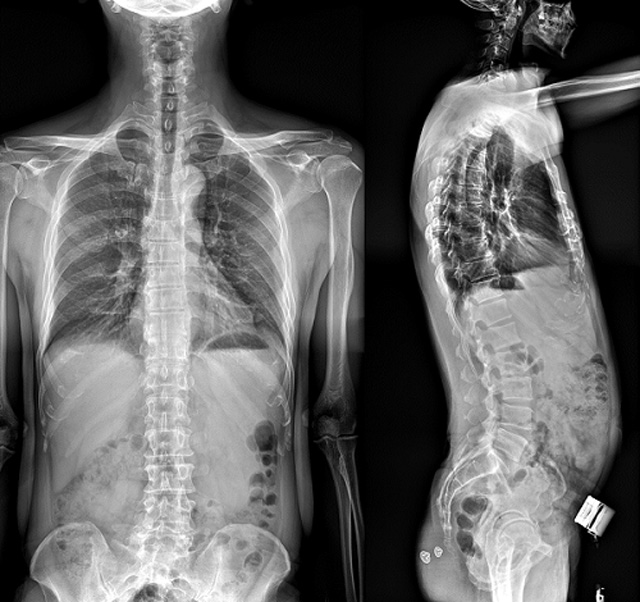

(7)全身拼接功能對有較大尺寸全脊柱拼接圖接桂成金下股分成幾次拍攝,再經(jīng)過秋件開在骨科開展的全脊柱畸形矯治工作中,雖然CT. MRI也能獲取全脊柱影像,接圖像,以便于長度、角度、力線等測量和察脊柱在重力情況下但不能進行立位檢查,無法觀全景觀察。全身拼接功能是高等級DR攝取患者立位全下的功能狀態(tài)圖像,因此采用動態(tài)醫(yī)院特別看重的動態(tài)DR功能之一。注:圖中Cobb脊柱正側位圖像是首選的檢查方法角度的大小是反映側彎嚴重程度的一個標準。